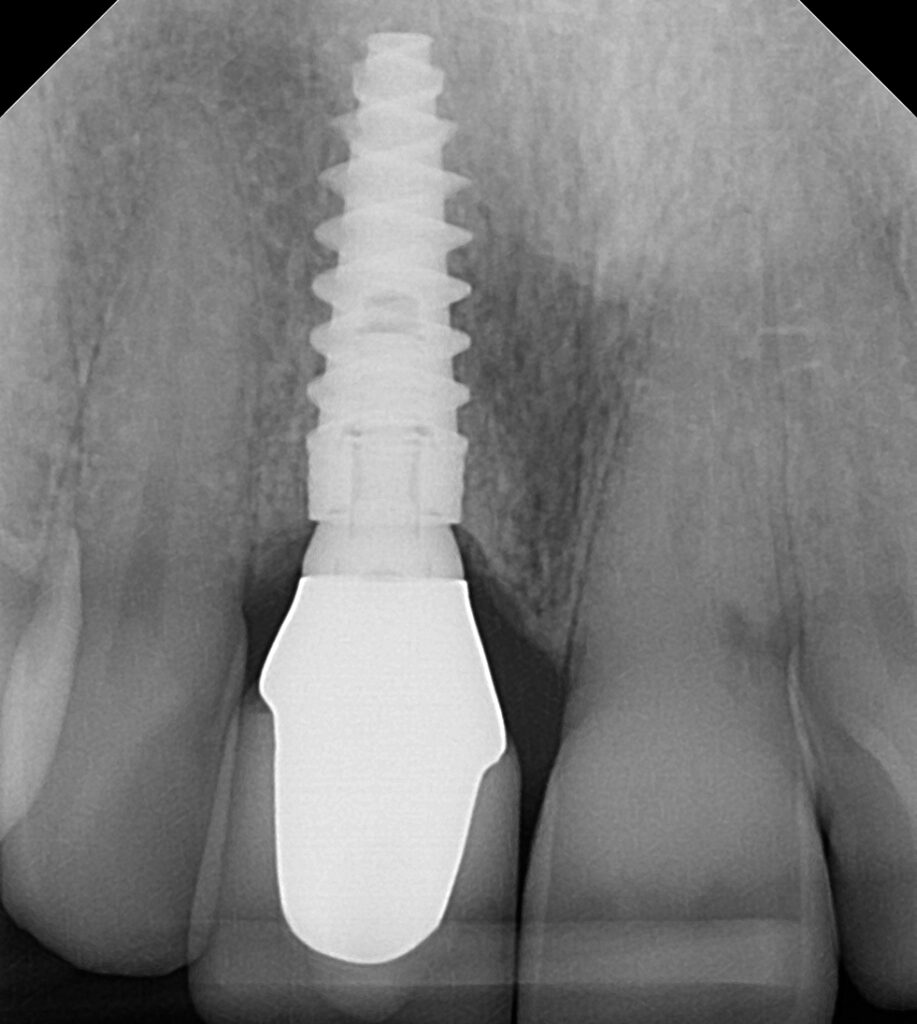

What Exactly is a Dental Implant?Think of a dental implant not as a false tooth, but as a complete prosthetic system designed to mimic your natural tooth from root to crown.

- The Root (The Implant Post): A small, incredibly strong, biocompatible titanium post is surgically placed into your jawbone. This isn’t just an anchor; it’s a new artificial root.

- The Foundation (Osseointegration): This is the magic. Over a few months, your jawbone naturally fuses with the titanium post in a process called osseointegration. This creates a rock-solid, permanent foundation that is actually stronger than a natural tooth root.

- The Crown (The Visible Tooth): Once the foundation is secure, a meticulously crafted, natural-looking porcelain crown is attached to the post. This crown is custom-shaped and shaded to blend seamlessly with your smile, making it indistinguishable from your natural teeth.